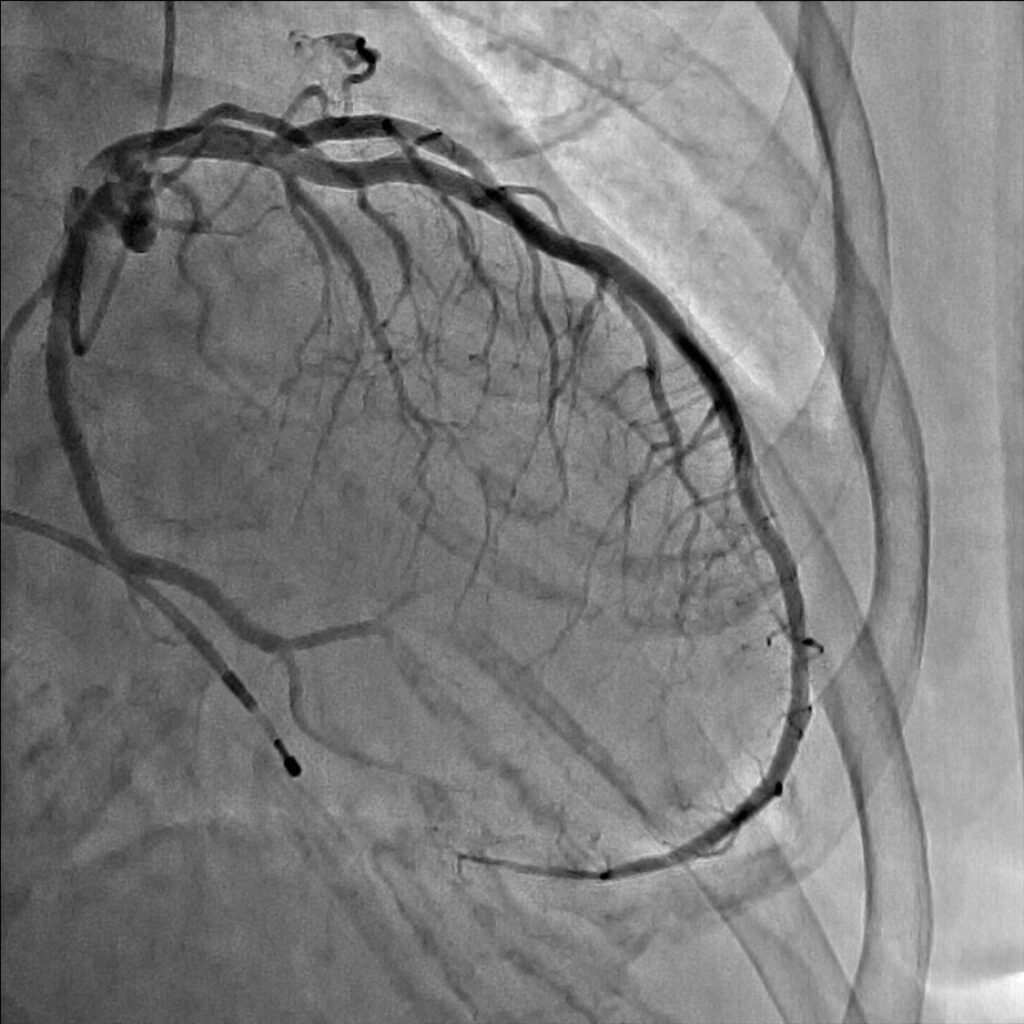

妻の勧めで近所の医院を受診しました。安静時心電図検査では何の異常もなかったのですが、念のためにと私の外来を紹介されました。ベルトコンベアーの上を歩く運動負荷心電図検査でいつもと同じような症状を覚え、心電図に異常が出現しました。私は労作性狭心症と診断しました。手首からカテーテルを挿入した冠動脈造影検査で、一番大きな冠動脈枝の近位部に高度な狭窄が見つかりました。後日、風船とステントを用い、狭窄を開大しました。症状は完全に消失し、今は農作業に精を出しています。

狭心症は“心臓を狭める”という症状から由来した病名です。疑わしい症状がある方は、上記の症状に合致するかをチェックしてみて下さい。専門医は症状を詳細に聴取するだけで80%以上の診断が可能です。労作性狭心症を裏付ける検査としては、運動負荷試験が最も一般的です。心電図や血圧計を装着し、ベルトコンベアーの上を歩きます。速度や勾配を段階的に上げることで心筋に徐々に負荷をかけていきます。いつもの症状が出たとき、心電図異常が出現したとき、負荷が標的水準までかかったときに中止します。この検査は診断率が高くかつ安全です。最終的には造影剤を使ったCT検査やカテーテル検査で狭心症の診断のみならず、冠動脈狭窄の程度や部位、病変部数等を精査します。

治療はカテーテルを使い風船やステントで狭窄部を拡張し、血液の流れをよくすることが一般的です。冠動脈の全ての枝に狭窄がある方、あるいは左主幹部と呼ばれる最も太い血管と他の枝に病気が重複している重症な方等には冠動脈バイパス手術をお勧めしています。しかし、症状が無い方や心筋虚血を心電図等で客観的に認めない方は、冠動脈に狭窄があっても、こうした治療をせず悪玉コレステロールを下げる、高血圧をコントロールする、禁煙をする、糖尿病のコントロール等の冠動脈硬化の危険因子を治療することで経過をみることも多いです。